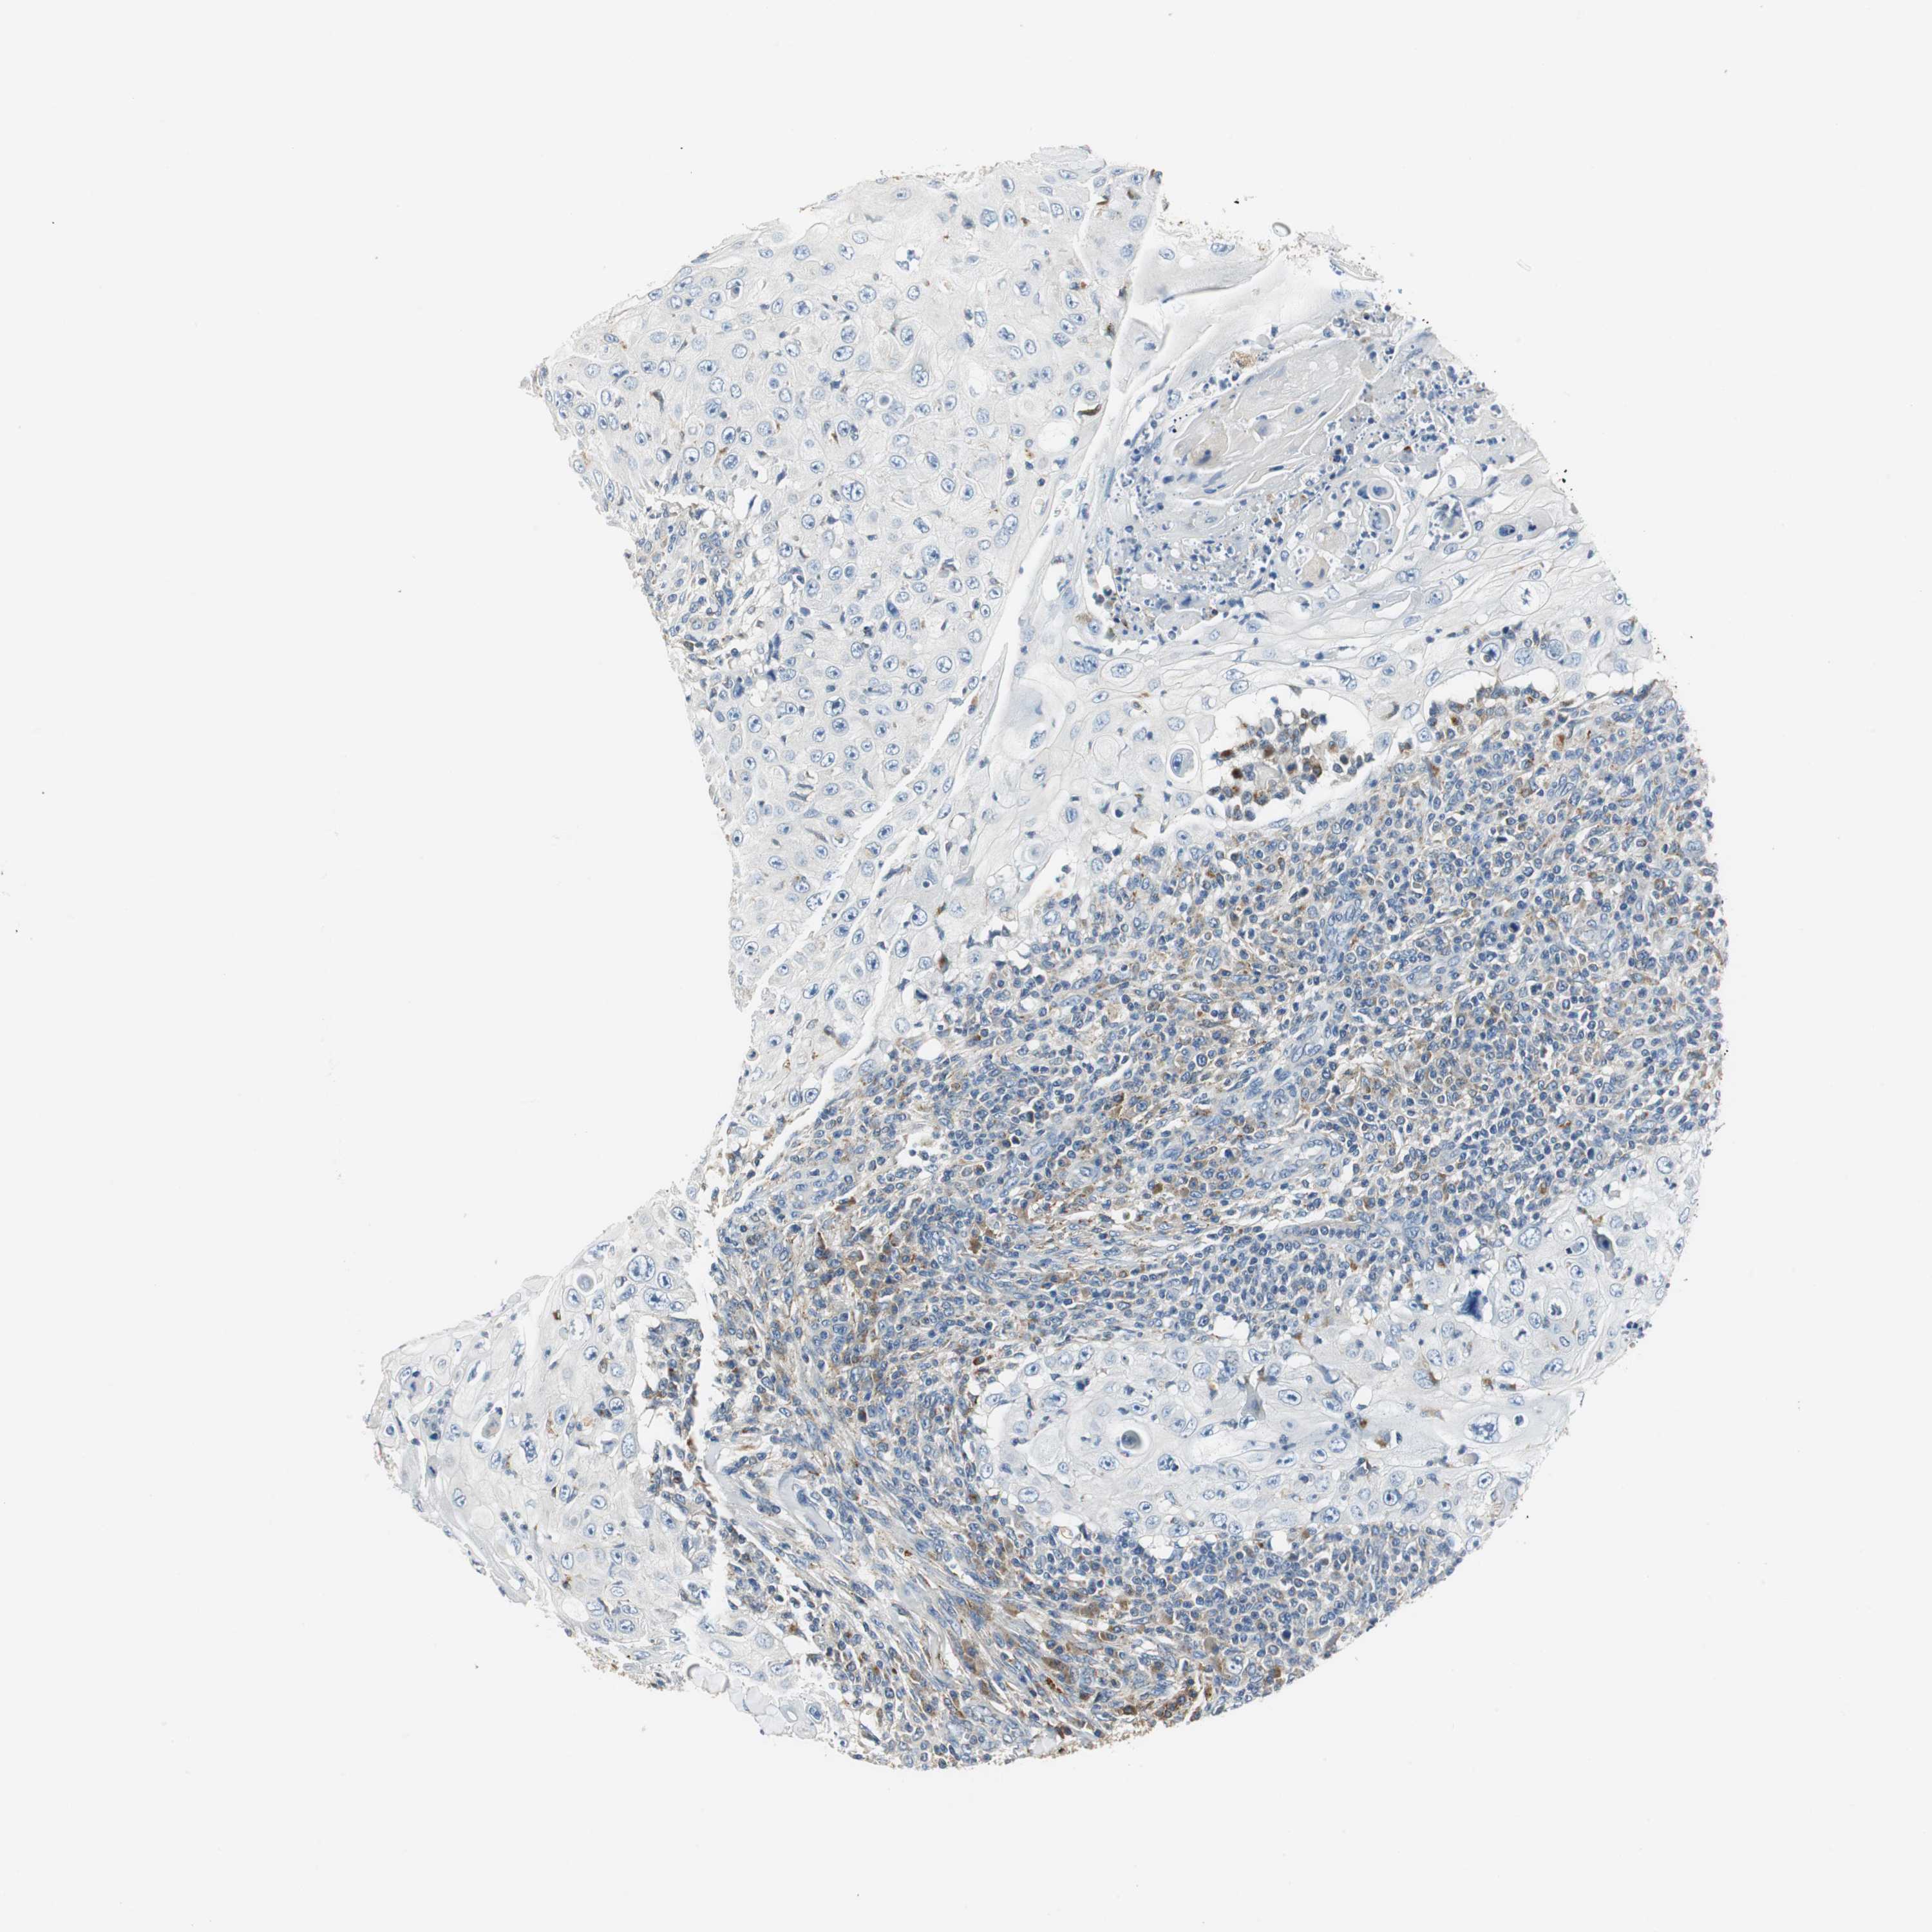

SKIN CANCER - Protein expressioni

A mouse-over function shows sample information and annotation data. Click on an image to view it in a full screen mode. Samples can be filtered based on level of antibody staining by selecting one or several of the following categories: high, medium, low and not detected. The assay and annotation is described here.

Antibody stainingi

Antibody staining in the annotated cell types in the current human tissue is reported as not detected, low, medium, or high, based on conventional immunohistochemistry profiling in selected tissues. This score is based on the combination of the staining intensity and fraction of stained cells.

Each image is clickable and will lead to virtual microscopy that enables deeper exploration of all samples and also displays staining intensity scores, fraction scores and subcellular localization as well as patient and tissue information for each sample.

Antibody HPA006657

Staining

High

Medium

Low

Not detected

Intensity

Strong

Moderate

Weak

Negative

Quantity

>75%

75%-25%

<25%

None

Location

Nuclear

Cytoplasmic/membranous

Cytoplasmic/membranous,nuclear

Squamous cell carcinoma, NOS

Basal cell carcinoma